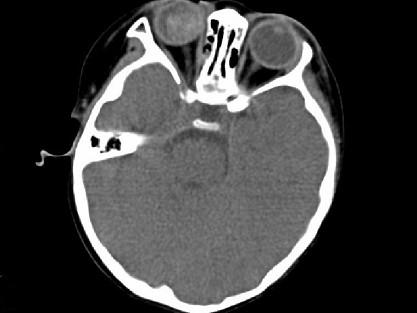

问题 男,2岁、右眼白瞳症一个月,CT影像如图,最可能的诊断为 ( )

选项 A、Coats病 B、视网膜母细胞瘤 C、永存原始玻璃体增生症 D、脉络膜骨病 E、眼球内寄生虫病

答案 B